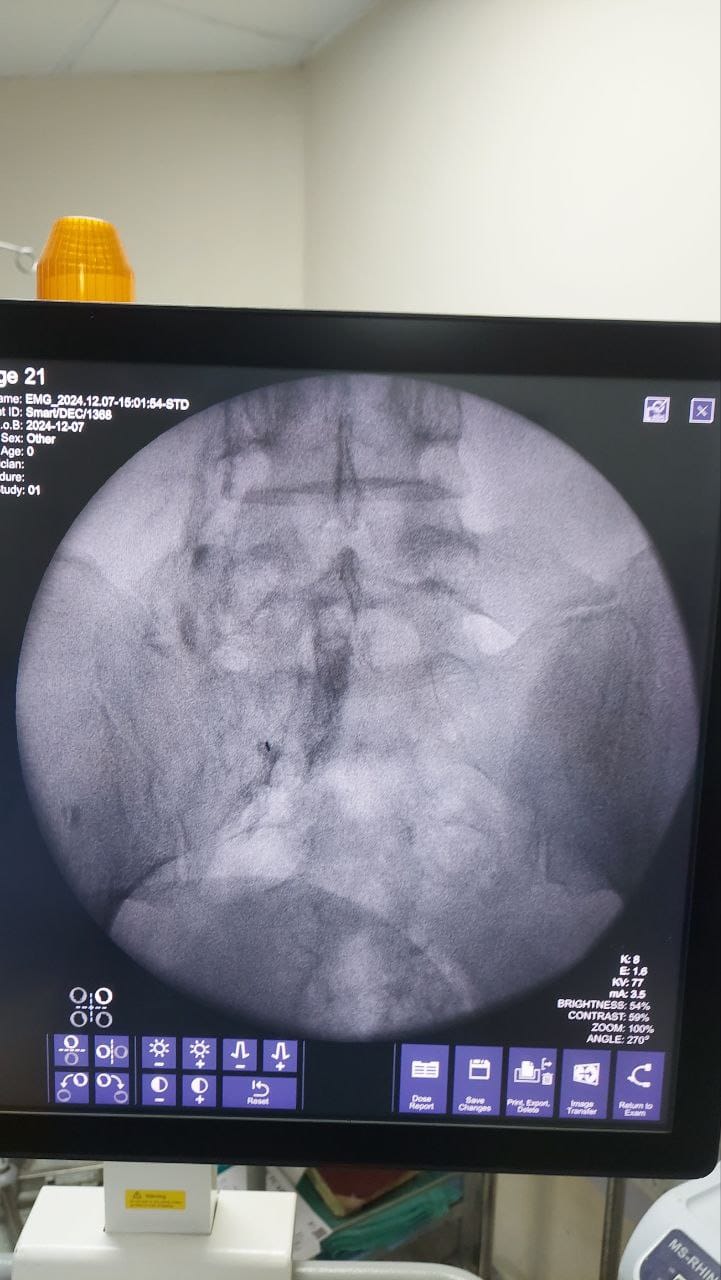

Procedures

Struggling with chronic pain? Get advanced, personalised pain management from Dr. Manish De, one of Kolkata’s leading pain specialists. From knee pain, heel pain, low back pain, frozen shoulder, migraines, cancer pain to post-TKR persistent pain—Dr. De offers safe, evidence-based treatments across multiple locations: